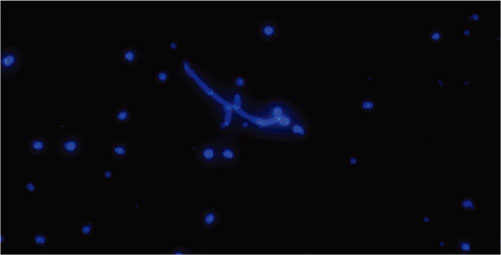

镜下图像背景低对比度高,能清晰的呈现出真菌的外形轮廓

清晰、真菌(菌丝和孢子)在镜下为清晰的亮色

真菌孢子快速检测